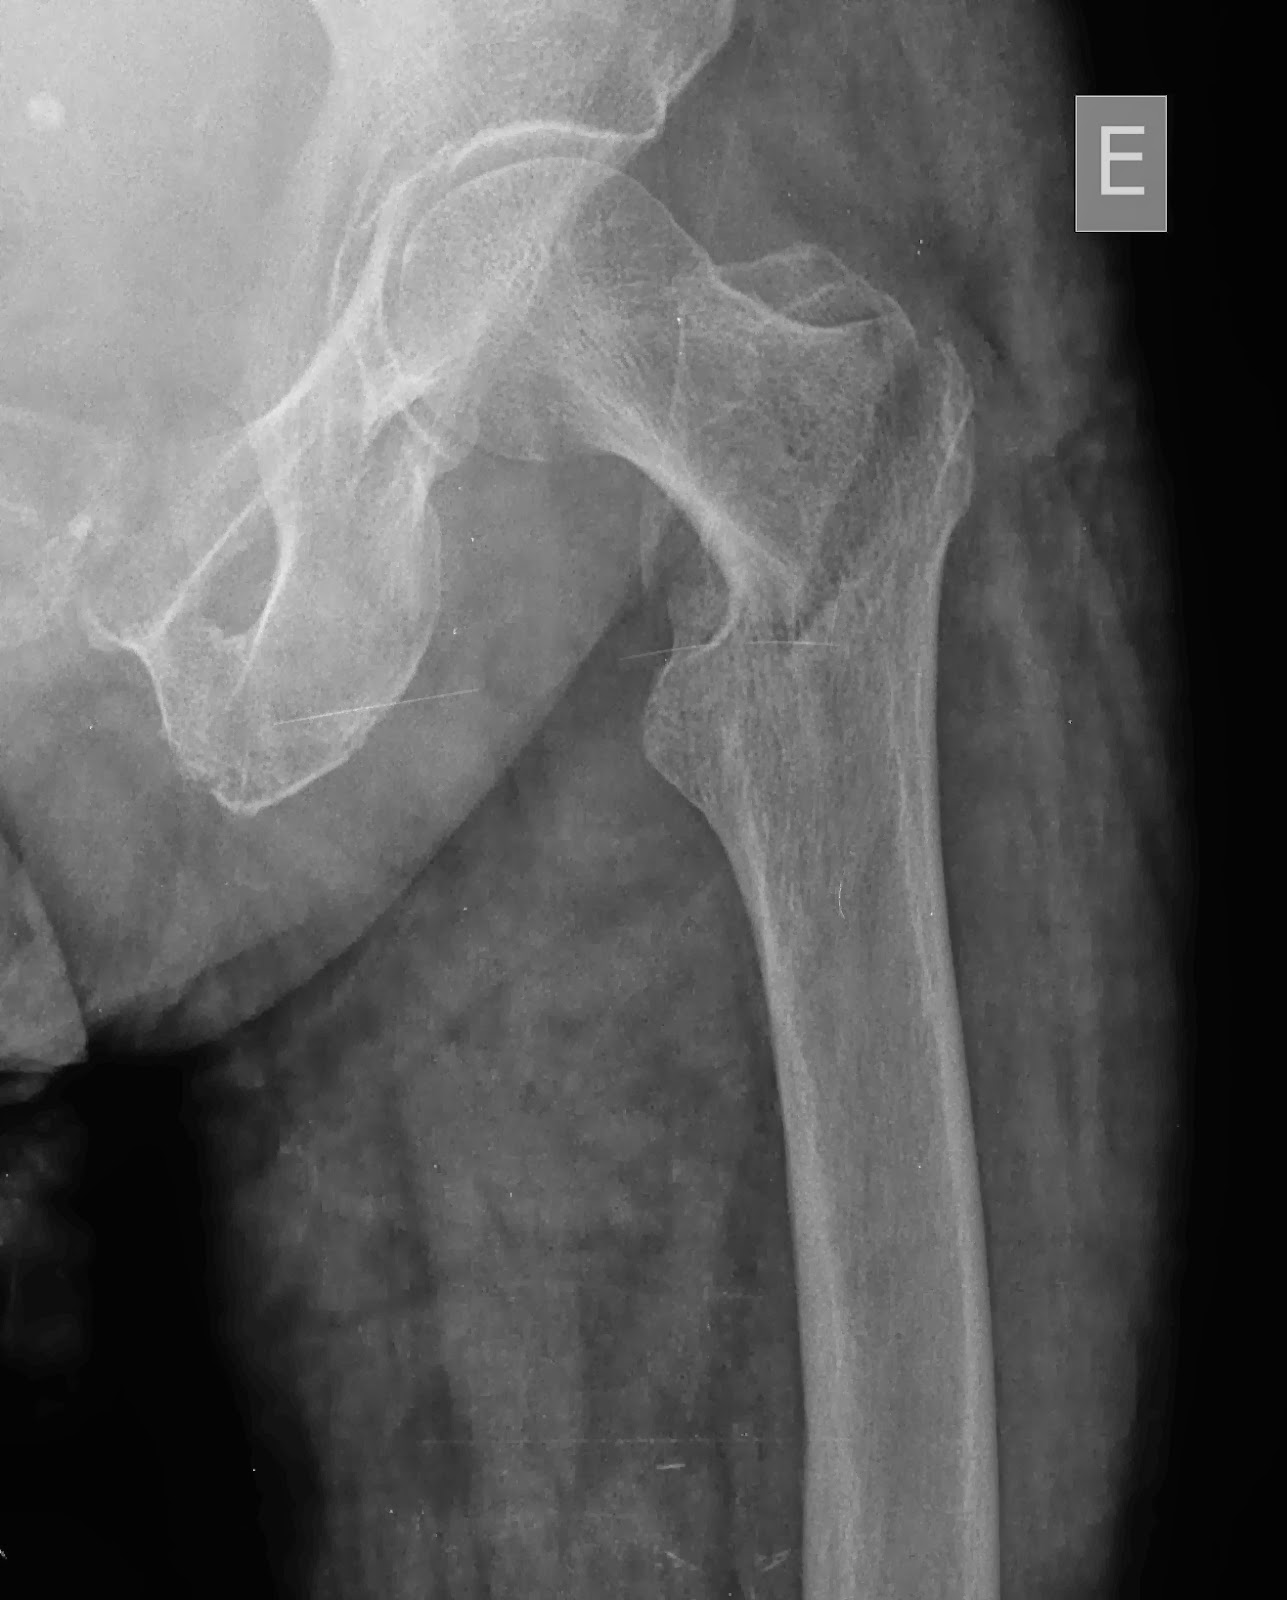

Rx de fémur A) AP; B) Lateral. Se observa lesión lítica mal... Download Scientific Diagram

Fraturas do Quadril Transtrocanteriana e Colo do Fêmur

Fractura do colo do fémur a direita, tipo Garden I e seu tratamento cirurgico Enfermagem em